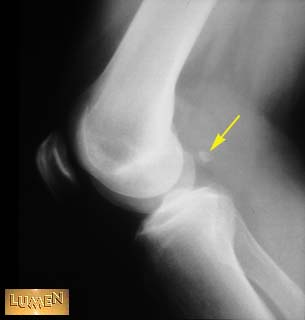

Fabella.

Lateral head of gastrocnemius m.